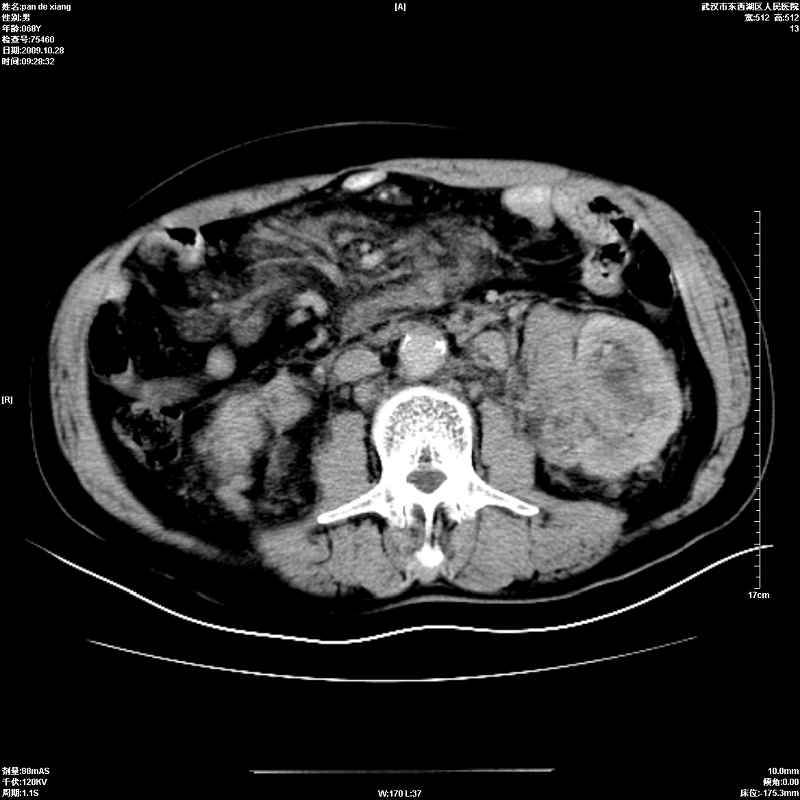

以下是引用杀毒软件在2009-10-28 20:41:00的发言:[br]结合临床考虑---白血病双肾改变或淋巴瘤。

以下是引用zxl51642在2009-10-29 9:59:00的发言:[br]结合临床“单克隆免疫球蛋白血症”,考虑双肾为继发损害并肾功能不全(尿中大量igg及少量iga、igm等大分子免疫球蛋白滤出所致继发损害),椎前软组织肿块为髓外造血。与浆细胞瘤有区别,平扫时有战友说的很清楚。